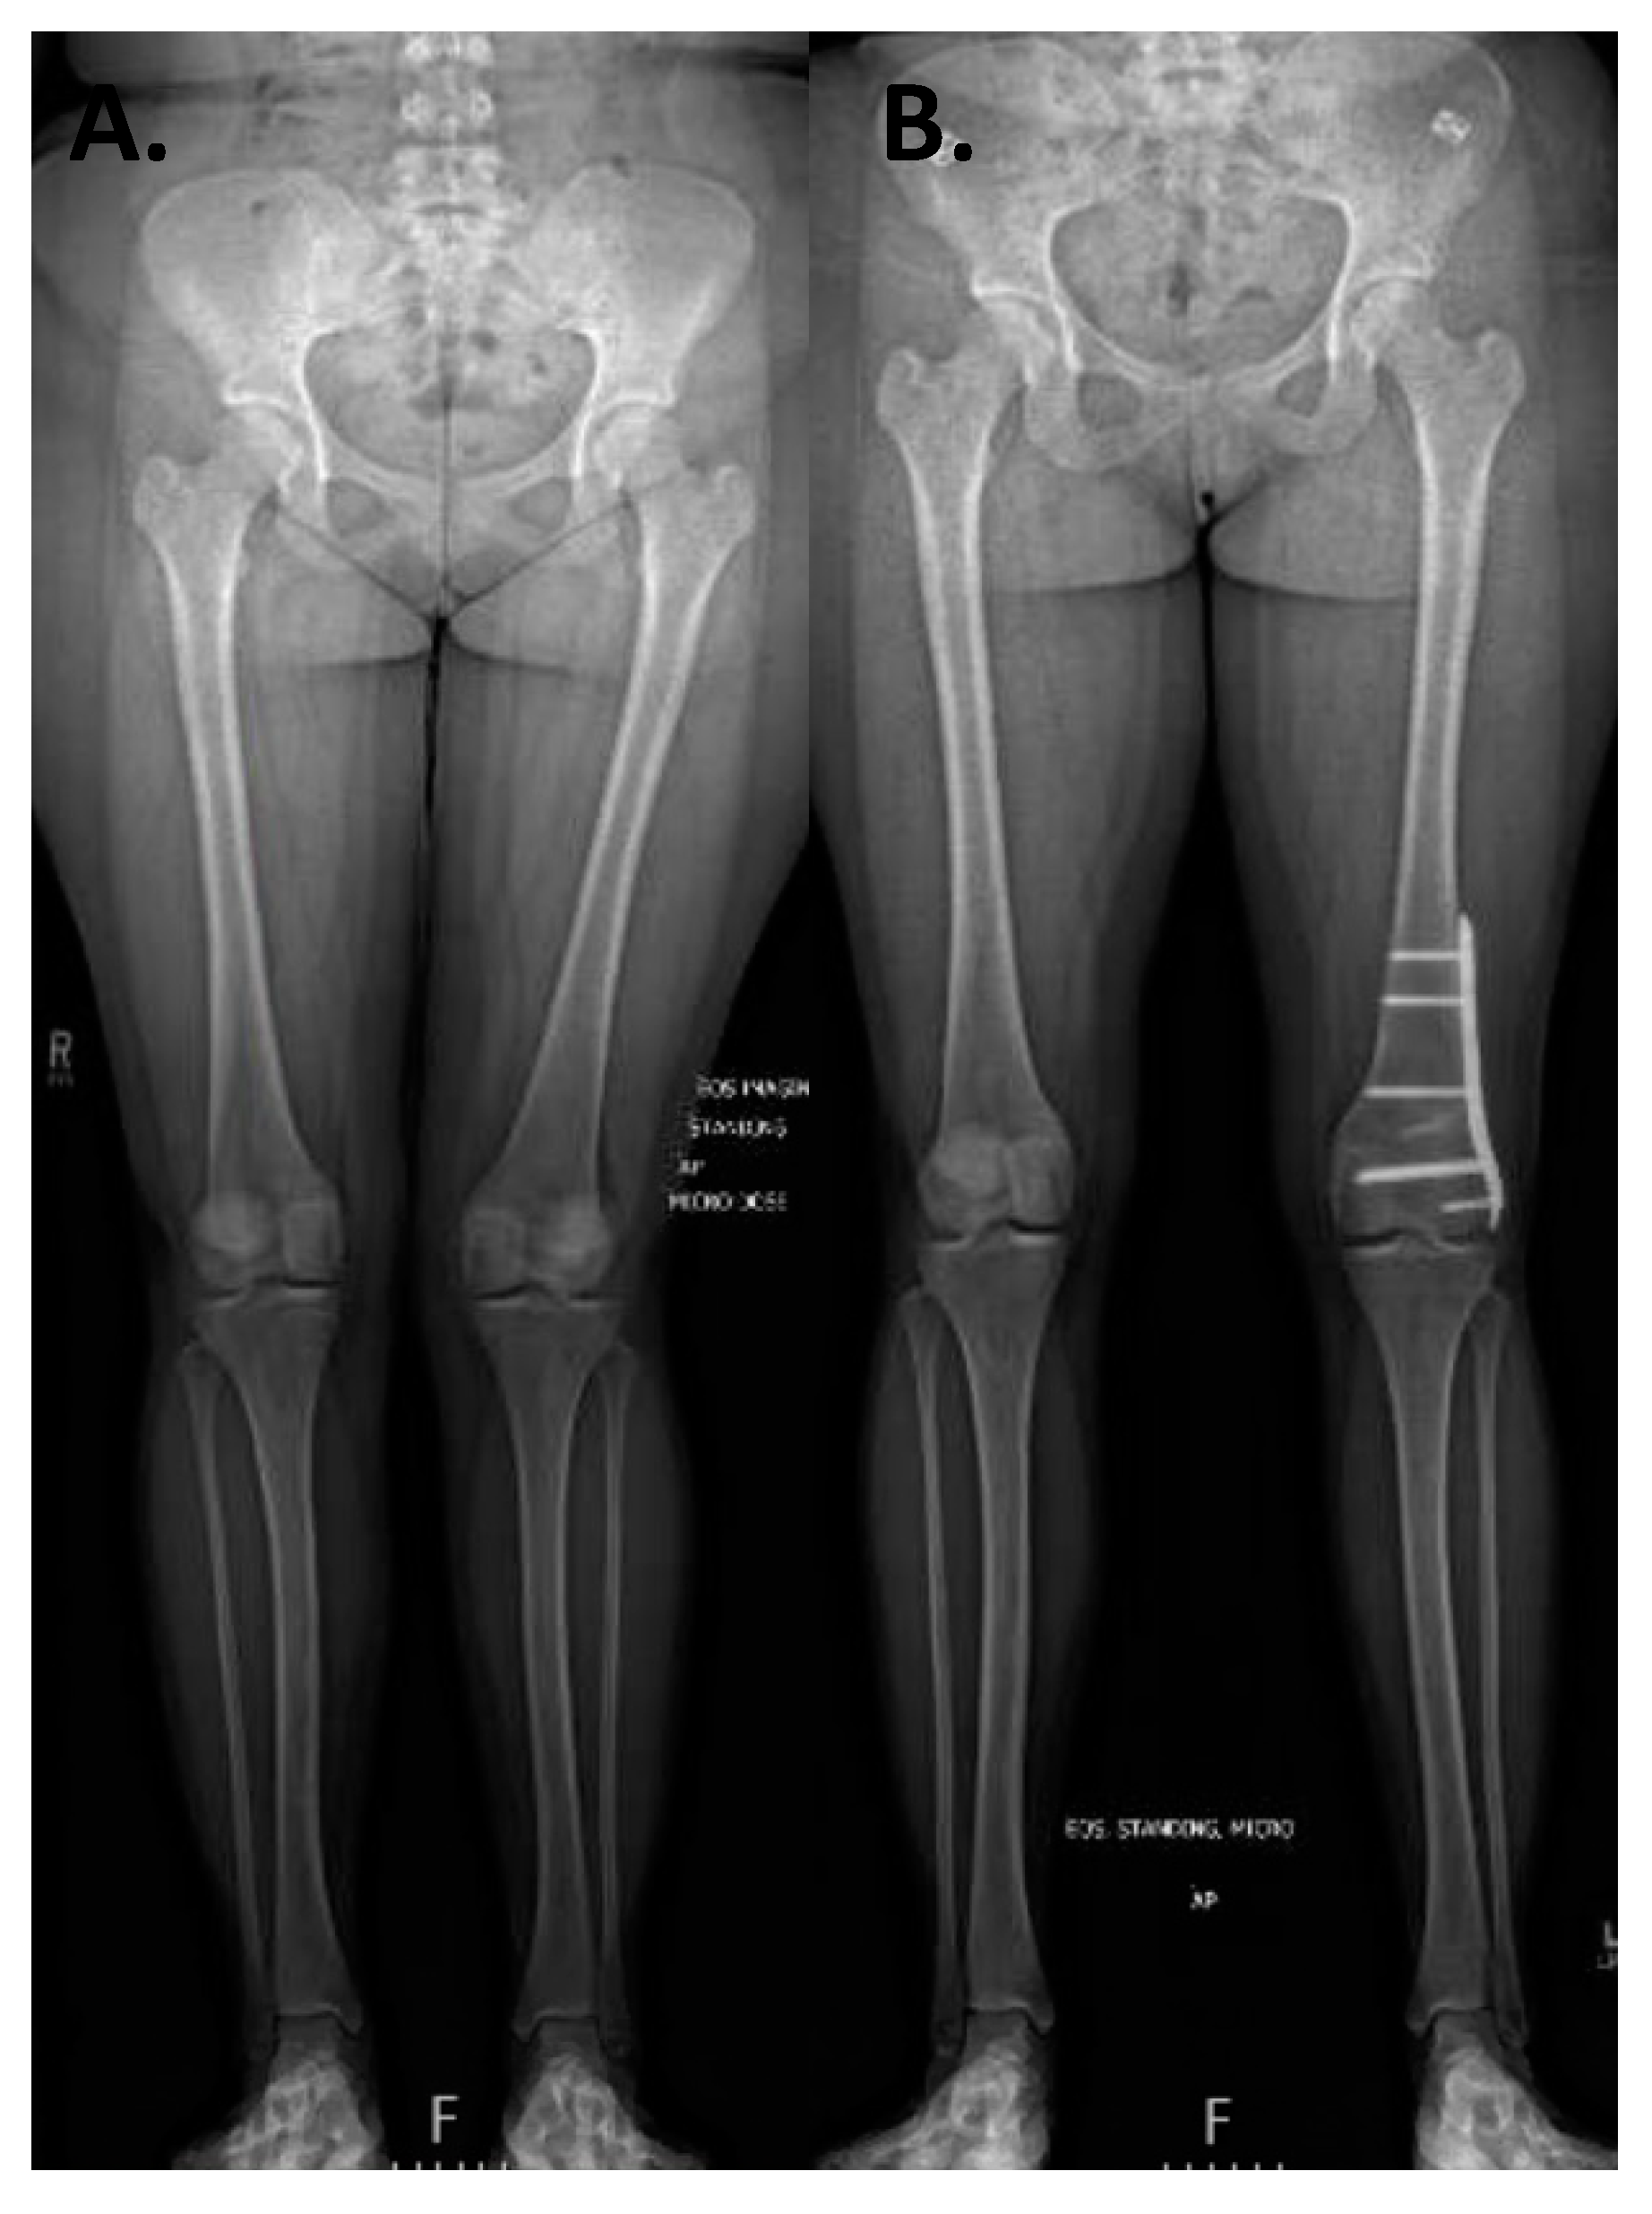

3.1. Coronal Plane Malalignment